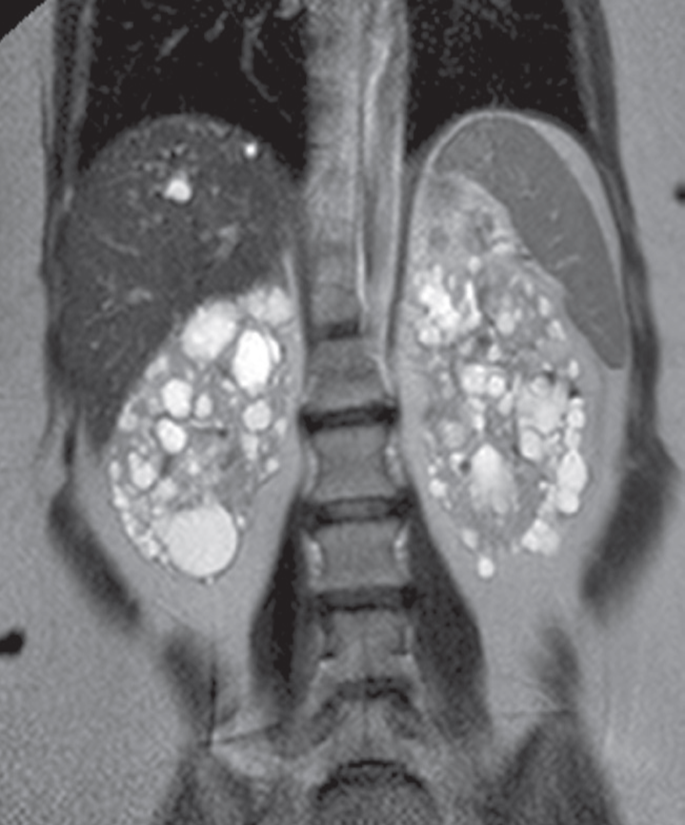

Coronal T2-weighted MRI

demonstrating multiple bilateral renal cysts as well as a few cysts in the liver.